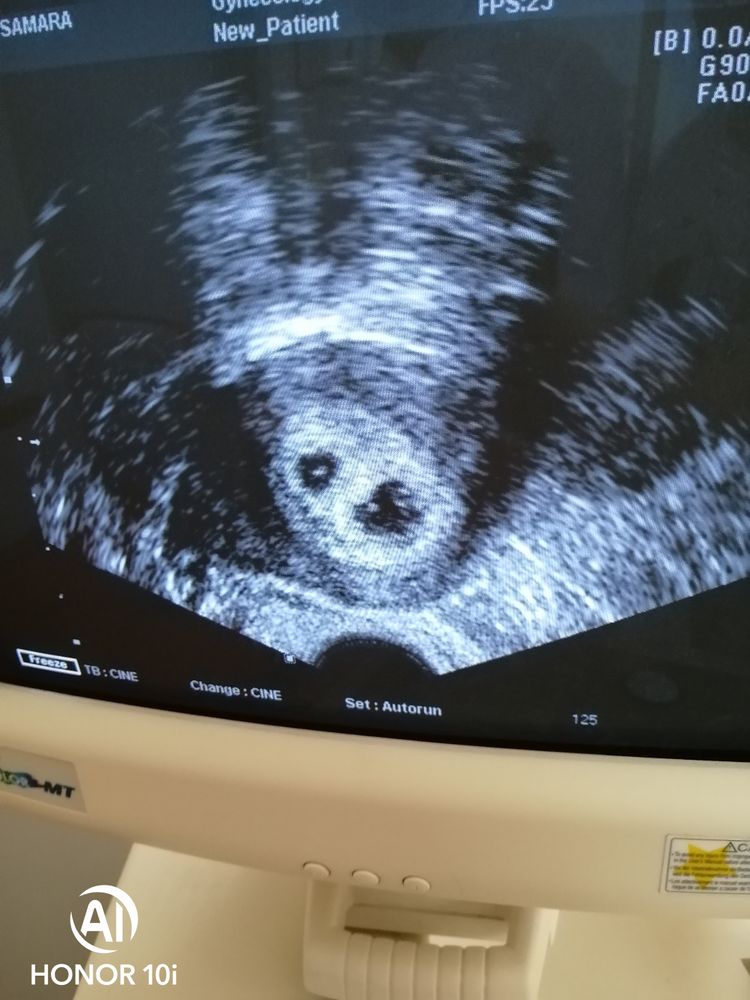

21 дпп, узи

Поздравляю с двойным счастьем!!! Кто у Вас врач был?)

Это чудо!!!! Дай Вам Бог обнять свое счастье через 8 месяцев! Скажите, а на 14 ДПП у вас какой был ХГЧ? Сейчас у вас есть признаки токсикоза?

Счастье пришло и в наш дом, спасибо! Хгч не 14 дпп-1303. Жуткая изжога от всего, и давление падает часто. Состояние как с бодуна🤣